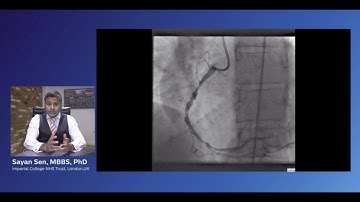

Integrating Philips iFR Co-registration into your workflow - Dr. Sayan Sen